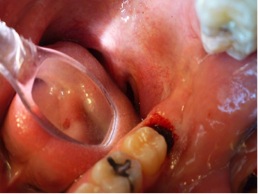

Fig 10. Excellent hemostasis after the completed ablation of the inflamed gingiva.

Figure 10

3. After the initial pass with the laser, the inflamed gingiva bled slightly and the surgeon defocused the beam by increasing the nozzle-to-tissue distance to quickly obtain hemostasis (Figure 10). Note the excellent visualization and the clear operatory field.